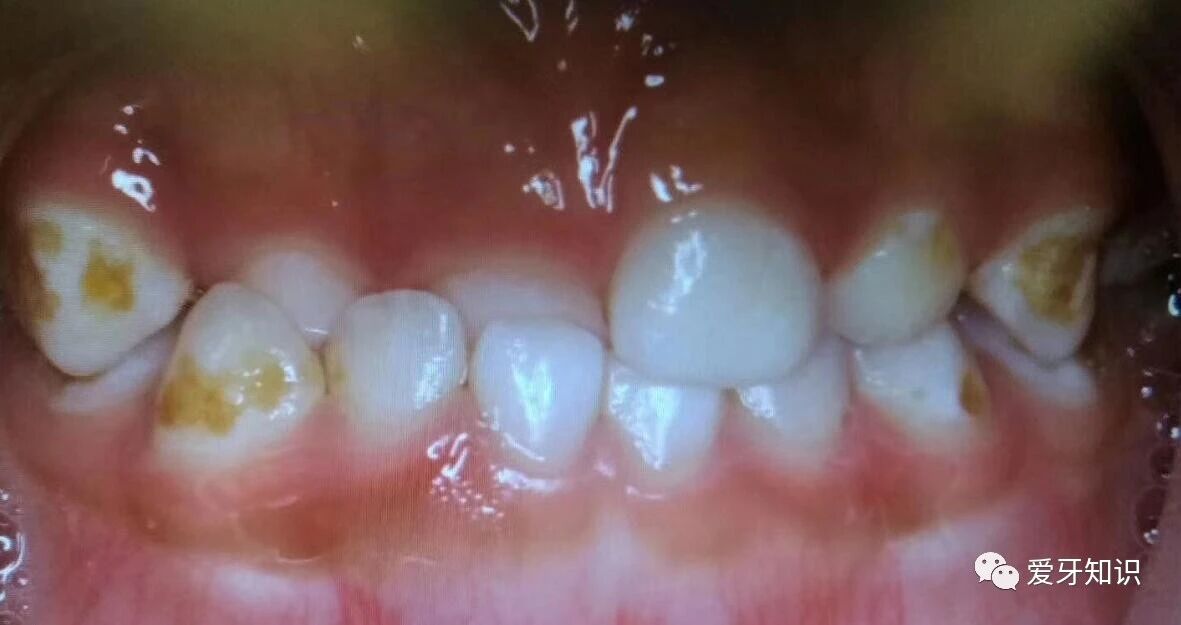

4影响口腔健康:

排列不齐的牙齿,容易积存食物,刷牙也刷不干净,易龋坏,牙周炎甚至牙周病

个别牙齿地包天。

前牙地包天。

当然开颌,龅牙,深覆颌,牙齿不齐拥挤,都可以早期干预矫正的。